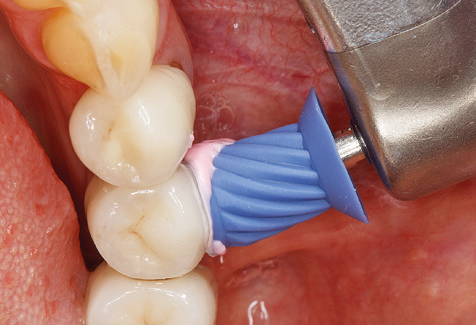

Fig. 4: Flexible probes with millimetre markings are recommended for the probing of dental implants (e.g. Colorvue Kit PCV11KIT6, Hu­Friedy). – Fig. 5a and b: A straight working tip (1P, W&H Dentalwerk Bürmoos GmbH) is a suitable instrument for use on all natural teeth. – Fig. 6: Curved working tips (3Pr/3Pl, W&H Dentalwerk Bürmoos GmbH) lend themselves to the processing of difficult-to-reach areas of the tooth and root surfaces (e.g. furcations). – Fig. 7: The tapered, hexagonal implant cleaning tip (1I, W&H Dentalwerk Bürmoos GmbH) permits atraumatic and efficient cleaning of the crown and abutment surfaces. – Fig. 8: Titanium and carbon curettes are suitable instruments for the manual cleaning of the implant surfaces.

Fig. 9: The accessible implant and tooth surfaces are polished with polishing cups and suitable polishing compounds. – Fig. 10: Repeat instruction in the use of appropriate aids for oral hygiene at home should also form part of SPT. – Fig. 11a and b: Clinical situation 12 years after insertion of the prosthetic restoration. During this period, only a veneering ceramic fracture on tooth 47 and the requirement for endodontic treatment of tooth 12 were observed. All restorations are still functioning as intended.

Following machine cleaning of the tooth and implant surfaces, the surfaces of the natural teeth are cleaned manually using standard hand instruments. When performing manual cleaning, particular attention must be given to maintaining the correct angle of application, appropriate sharpness, good support and working with the curette from apical to coronal. Either titanium or carbon curettes should be used for post-cleaning of the implant structures (Fig. 8). In addition to the use of ultrasonic devices, power jet devices can also be used in conservative dentistry. However, it must be taken into consideration that these procedures are not suitable for removing hard deposits and thus they cannot replace the use of hand instruments and ultrasonic instruments completely. In all cases, cleaning is followed by mechanical polishing of the accessible tooth and implant surfaces with polishing cups and polishing compounds (Fig. 9).